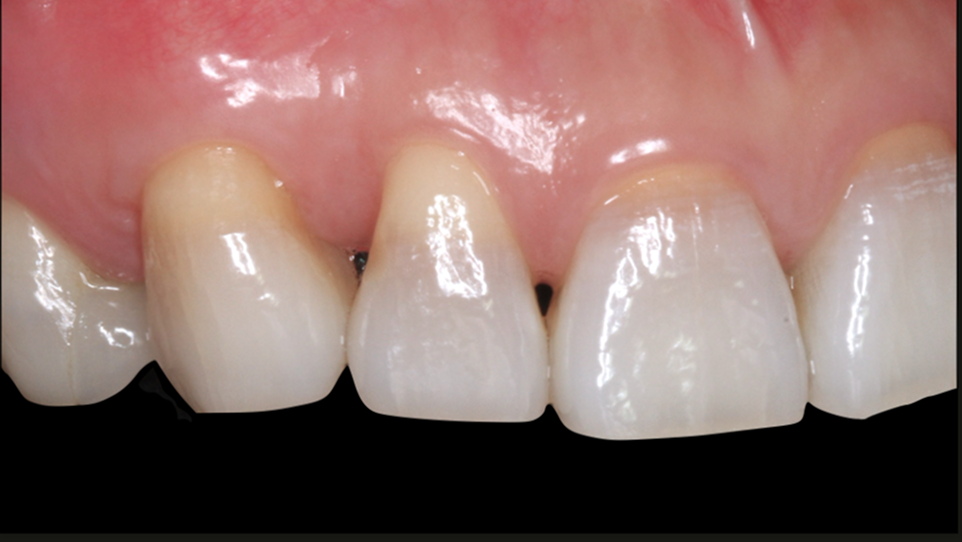

ガミースマイルを歯周形成外科で改善した症例

- 年代、性別 27歳・女性

- 来院動機 ガミースマイルを治したい

- 治療内容 歯周形成外科